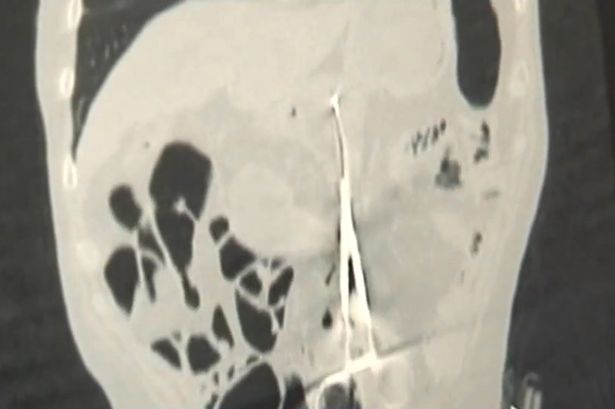

Nesposobni hirurzi ostavili su čovjeka da pati 12 godina od bolova u stomaku nakon što su slučajno ostavili makaze u njemu nakon jedne operacije. Karp Ponomaryov iz Kazahstana prije više od 10 godina podvrgnut je operaciji koja mu je spasila život, ali su mu u trbuhu ostavili makaze duge 20-ak centimetara.

Od tada je ovaj 53-godišnjak trpio strašne bolove nakon obroka, ali se nikad nije žalio na to jer je bio sretan da je ostao živ nakon operacije. Ljekarsku pomoć potražio je ponovo nedavno kada je izgubio apetit i počeo naglo mršati. Doktor Baurzhan Aybaev ostao je šokiran kad je vidio rendgenski snimak.

– Nikad nisam vidio ovakvo nešto. Nekad se desi da ostane neki mali dio hirurške opreme, ali da to budu makaze, to je nevjerovatan propust – rekao je doktor, te dodao: – Hirurgu koji mu je radio operaciju su očito promakle.